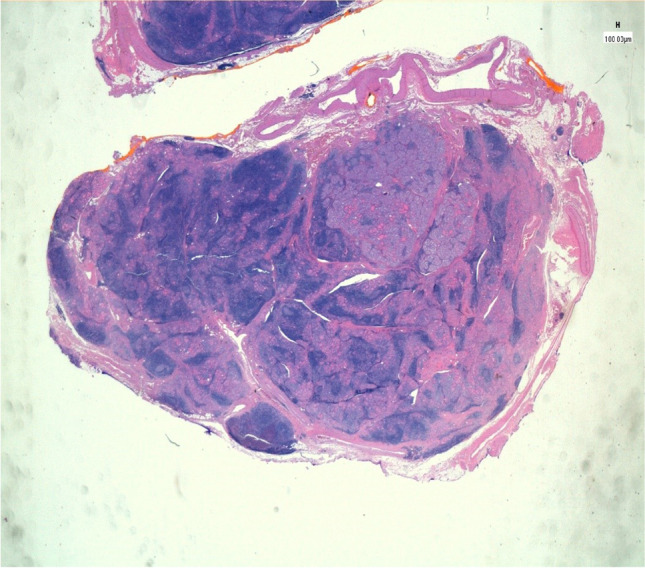

The co-occurrence of HT and PTC remains an active area of research, with conflicting data reported. It is still not known today whether autoimmune disease predisposes the development of cancer, or whether carcinogenesis induces the autoimmune response (Fig. 1).

Fig. 1.

The proliferation focus sharply standing out against the surrounding thyroid parenchyma, which shows a rich follicular lymphoid infiltrate